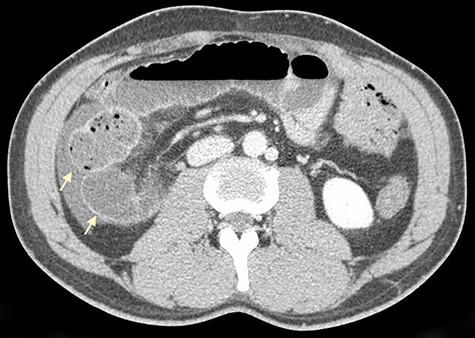

On physical examination, he was eupneic, hemodynamically stable and apyretic. His abdomen was soft, not distended, painless, with normal bowel sounds. Rectal examination showed an empty ampulla. Blood analysis revealed mild leukocytosis and little increase in C-reactive protein. Plain radiograph of the abdomen revealed dilated small bowel loops with air/fluid levels. Abdominal ultrasound revealed swollen intestinal loops on the right flank and interloop fluid. For further clarification, abdominal and pelvic computed tomography (CT) scan showed small bowel distension, air/fluid levels and free fluid (Fig. 1); signs of intestinal malrotation, with alteration of the normal topography of the duodenal arch (Fig. 2) and retrocecal position of terminal ileum (Fig. 3).

Axial CT scan shows retrocecal position of terminal ileum and free fluid in the right abdominal quadrants (arrows).